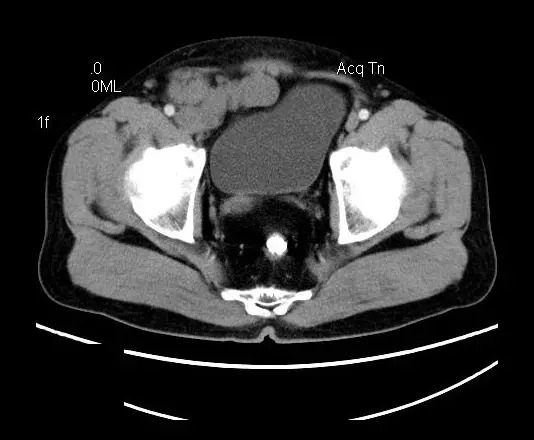

【影像表现】

盆腔右前侧及邻近腹股沟区可见多发大小不等的聚集生长的结节影,病灶呈软组织密度,边缘尚规整,分界尚清,增强扫描可见不均匀强化。膀胱局部受压,盆腔未见明显肿大淋巴结影。